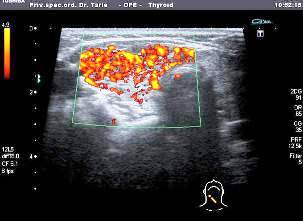

sl. 2. UZ Štitaste žlijezde